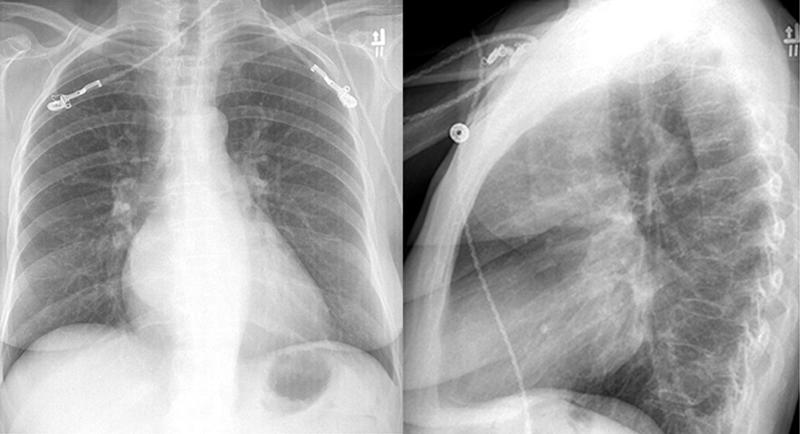

Mitral Valve Disease

Case 2 PA and Lat